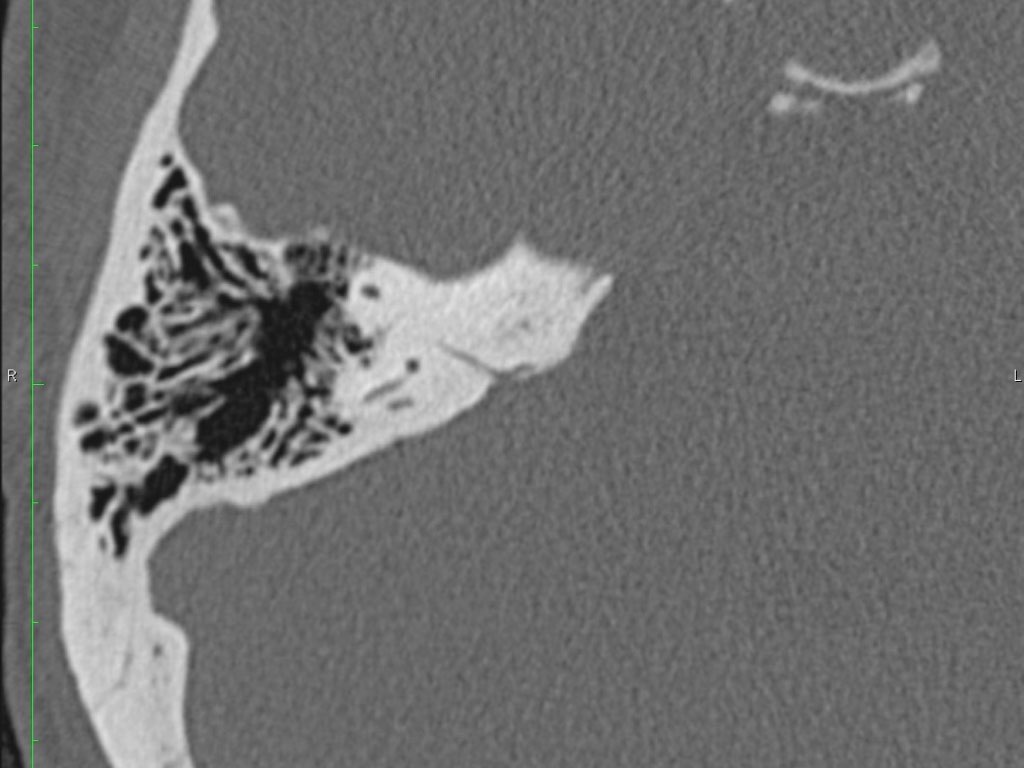

Trong bài tổng quan này, chúng tôi trình bày giải phẫu bình thường trên mặt phẳng cắt ngang (axial) và mặt phẳng cắt đứng ngang (coronal) của xương thái dương thông qua việc duyệt qua các hình ảnh.

Tai giữa bao gồm hòm nhĩ và hang chũm.

Hòm nhĩ là phần chính của tai giữa và chứa các xương con.

Thông qua ngách thượng nhĩ (aditus ad antrum), hòm nhĩ thông với hang chũm — một tế bào khí lớn nằm phía trên và phía sau hòm nhĩ — và thông với các tế bào khí chũm.

Giải phẫu xương đá trên mặt phẳng cắt ngang (Axial)

Nhấp vào hình ảnh để phóng to.

Cuộn qua các hình ảnh.